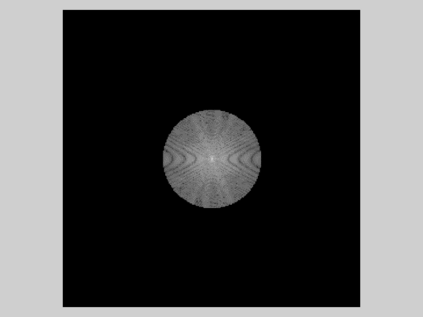

Reconstructing magnetic resonance (MR) images from undersampled data is a challenging problem due to various artifacts introduced by the under-sampling operation. Recent deep learning-based methods for MR image reconstruction usually leverage a generic auto-encoder architecture which captures low-level features at the initial layers and high?level features at the deeper layers. Such networks focus much on global features which may not be optimal to reconstruct the fully-sampled image. In this paper, we propose an Over-and-Under Complete Convolu?tional Recurrent Neural Network (OUCR), which consists of an overcomplete and an undercomplete Convolutional Recurrent Neural Network(CRNN). The overcomplete branch gives special attention in learning local structures by restraining the receptive field of the network. Combining it with the undercomplete branch leads to a network which focuses more on low-level features without losing out on the global structures. Extensive experiments on two datasets demonstrate that the proposed method achieves significant improvements over the compressed sensing and popular deep learning-based methods with less number of trainable parameters. Our code is available at https://github.com/guopengf/OUCR.